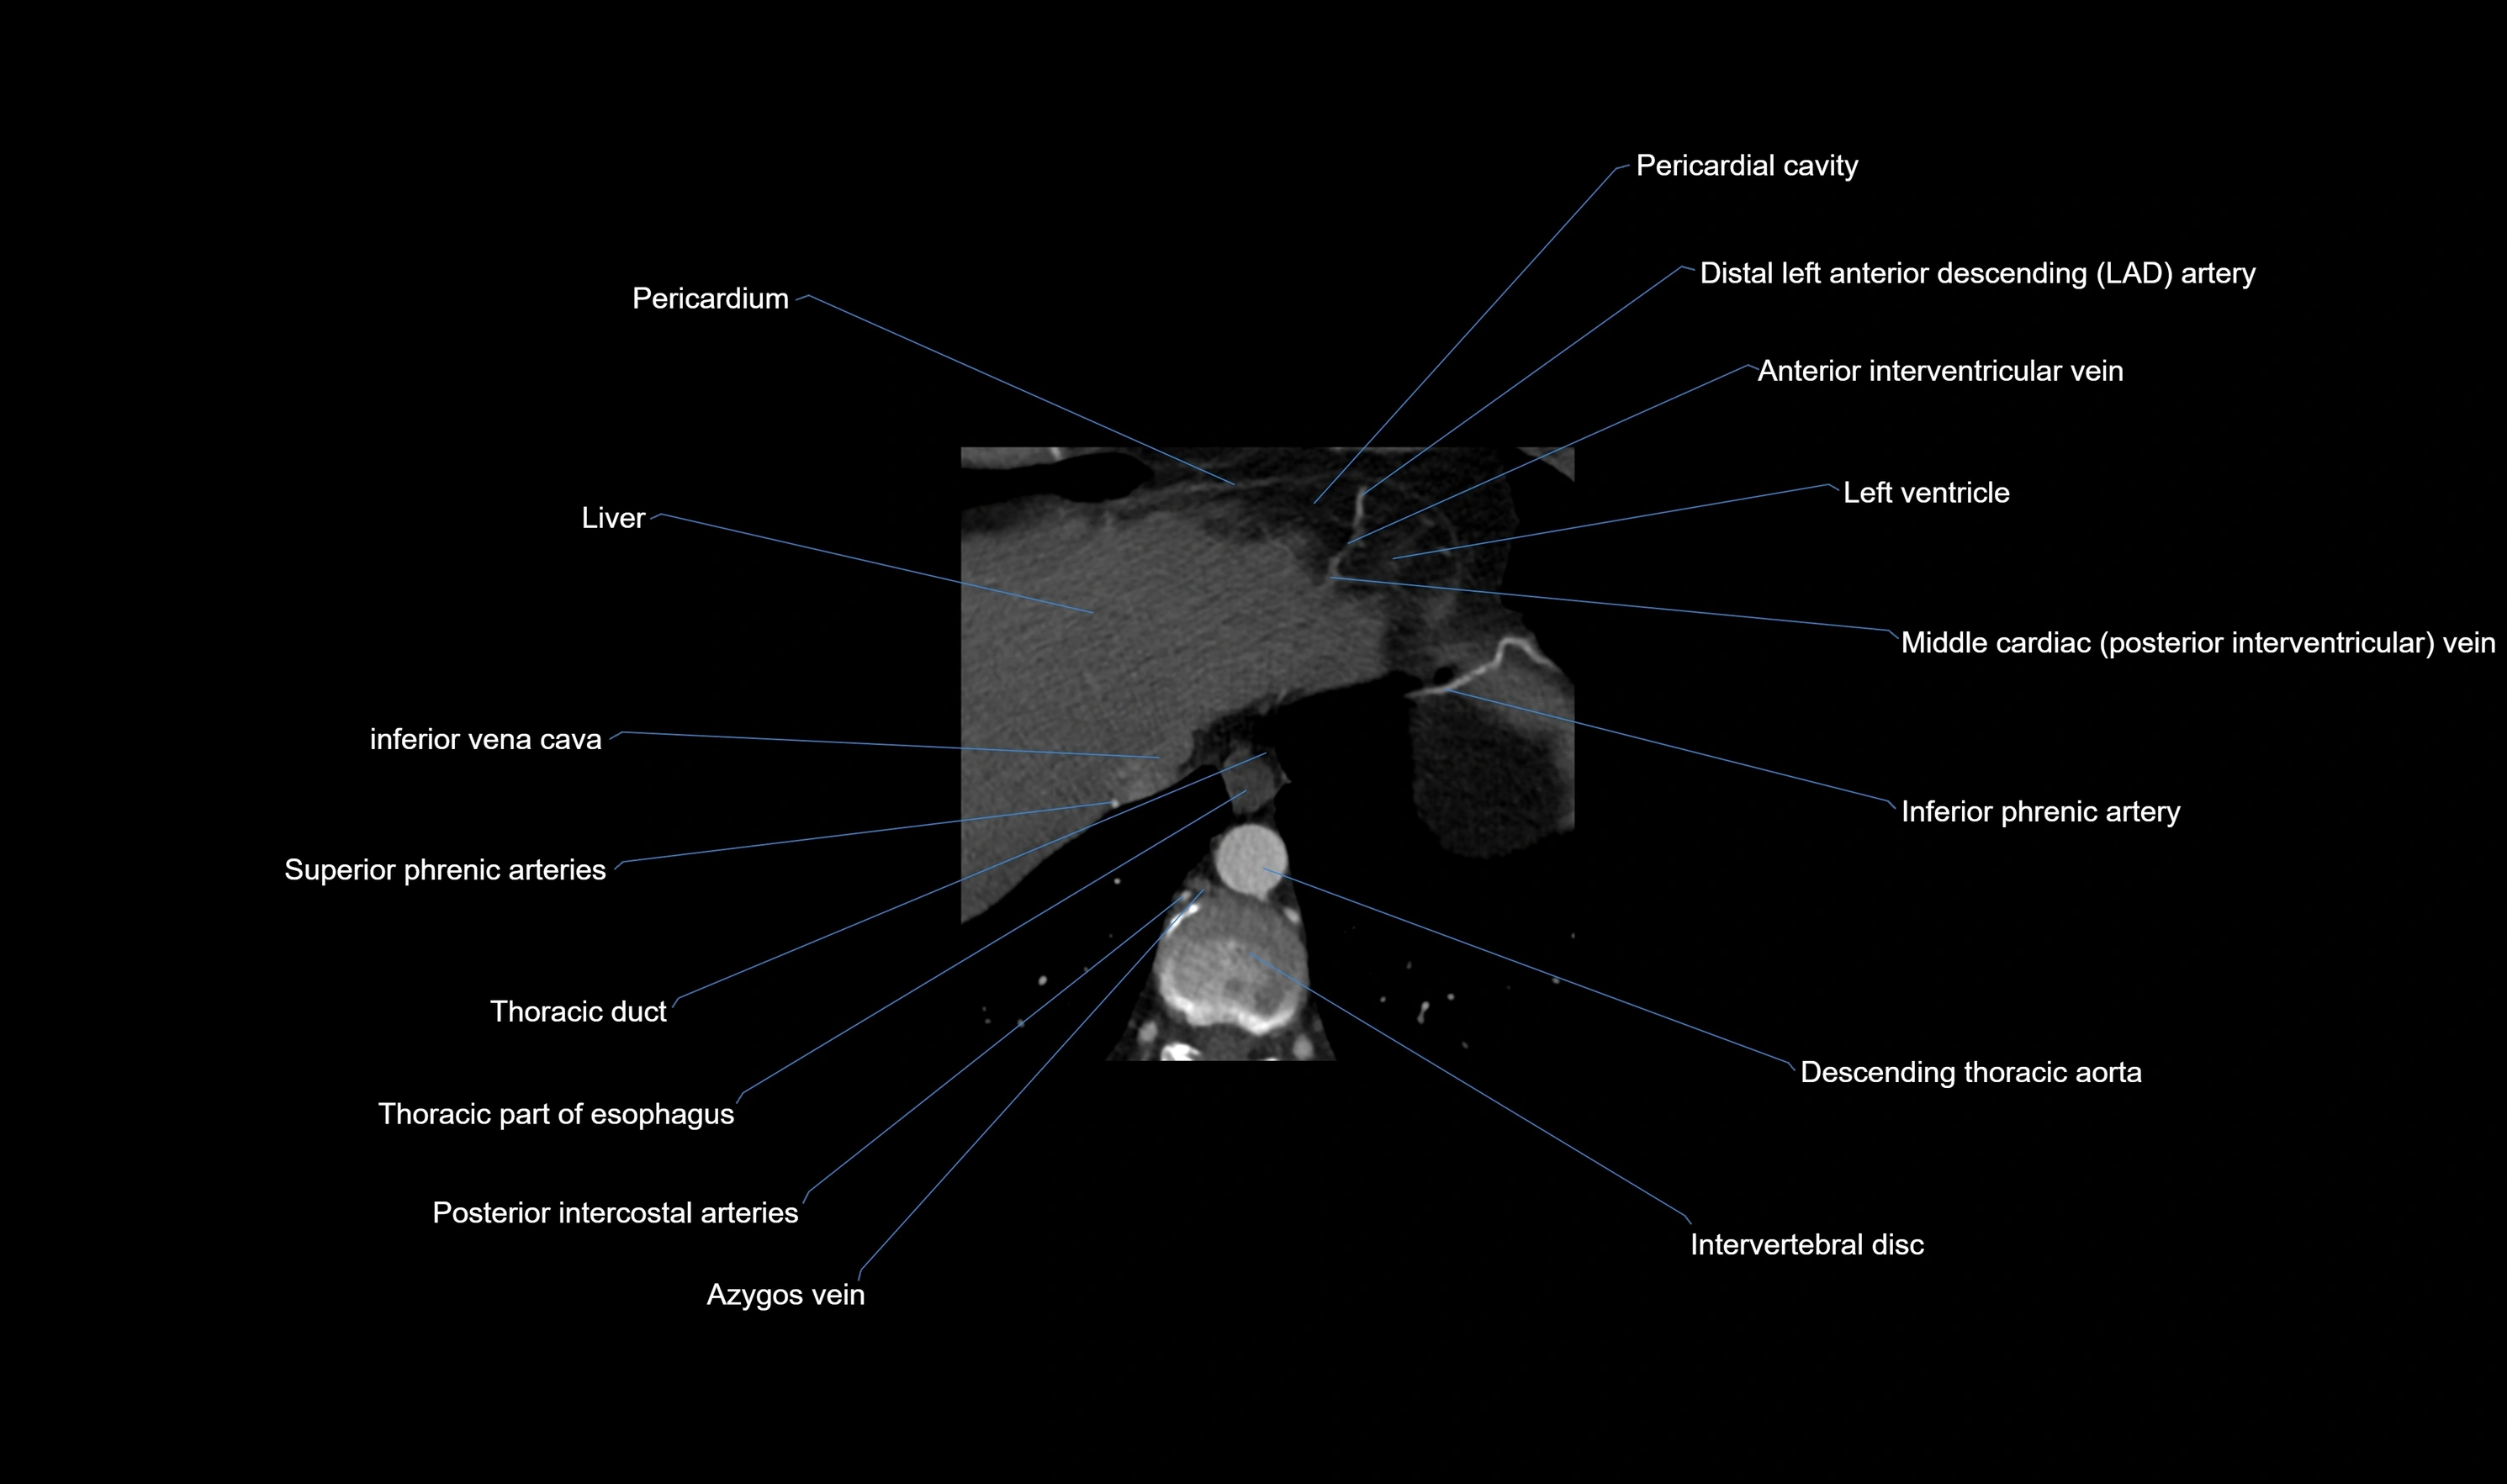

CT Coronary Angiography (CCTA):

Best non-invasive modality for acute marginal artery visualization

Shows origin, course along the acute margin, and right ventricular branches

Detects stenosis, occlusion, calcified and non-calcified plaques, aneurysm, or anomalous course

Multiplanar reformats and 3D reconstructions help in pre-PCI and surgical planning

Critical for assessing right ventricular infarction risk in RCA disease